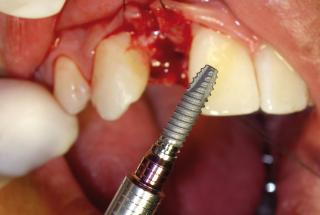

Clinical cases

MPI closely monitors clinical cases in the market to ensure their correct functioning and successful outcome.